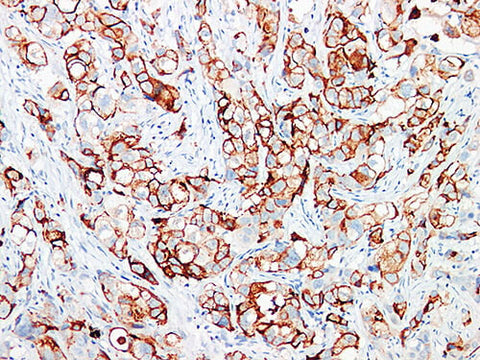

GCDFP-15 Monoclonal Antibody stored at 2~8°C

Applications IHC-P

Tissue Specificity Breast cancer

GCDFP-15 is expressed in the cytoplasm of parietal epithelium, lacrimal gland, cerumen gland, Moll's gland, mandible gland, tracheobronchial gland, sublingual gland and small salivary gland. GCDFP-15 can be used to judge breast cancer, salivary duct cancer and apical secretory epithelium.